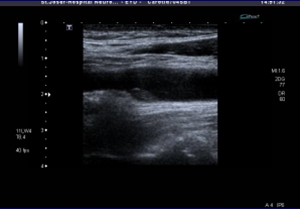

Εικόνα 4: Ασταθής υποηχογενής αθηρωματική πλάκα στον καρωτιδικό βολβό